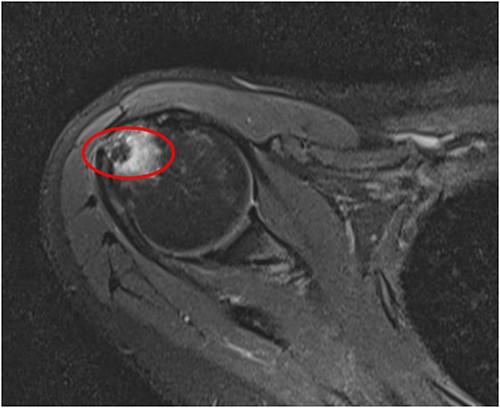

An MRI of the right shoulder showed calcifications over the supraspinatus tendon with an intraosseous lesion mimicking an aggressive or benign skeletal neoplasm (see Figs 2 and 3).

Axial T2 image of right shoulder showing hypointense lesion; note: the red circle indicates the intraosseous extension of calcified deposits originating from calcified supraspinatus tendon, with surrounding marrow edema.